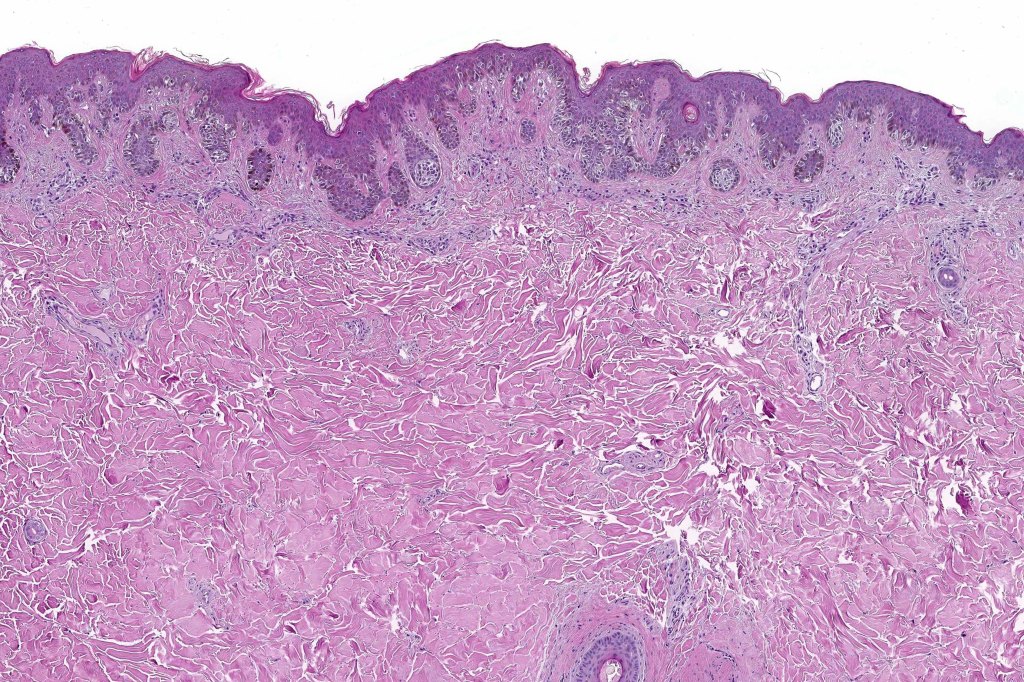

Histological features

•Architectural disorder- lentiginous and nested, nests abnormally located (at the sides of the rete ridges & overlying the dermal papillae in addition to the tips of the rete ridges rather than solely occupying the tips of the rete ridges as is seen in banal nevi), horizontal orientation & bridging between junctional nests (this should not be confused with bridging between adjacent rete ridge squamous epithelium)

•Host response- eosinophilic & lamellar fibroplasia, increased vascularity, lymphocytic infiltration & pigment incontinence

•In compound lesions, the nest size should be smaller than the junctional ones and the degree of atypia the same or less